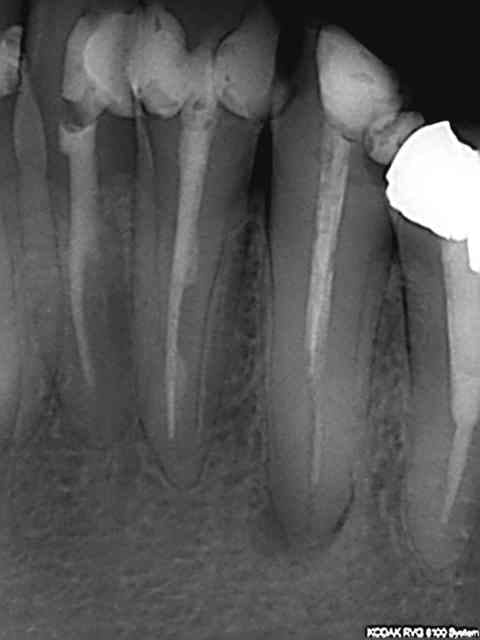

Sauf que si le mec développe une grosse pêche et dit que ce n'est pas par hygiène négligente mais parce que tu as bossé comme un sagouin, et qu'il porte plainte pour ça, on va te reprocher de pas avoir suivit les recommandations de bonne pratique (pas de clamp sur la radio, obturation à chier, etc), et ce sera à ta responsabilité pour faute et ta RCP de casquer (donc à toi indirectement, via augmentation des primes). Perte de chance, tout ça.